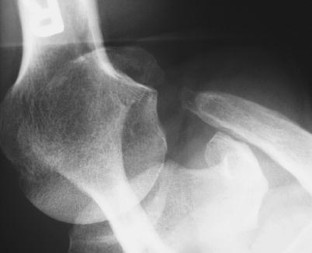

Abb. 1